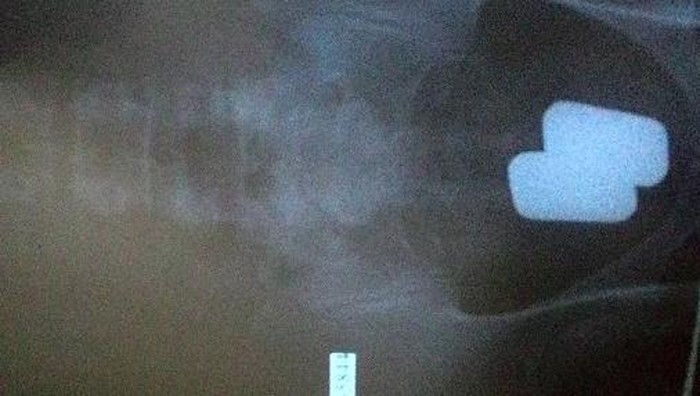

Mengetahui hal tersebut, pihak bea cukai bandara pun memaksa pria tersebut untuk mengeluarkan emas tersebut di toilet. Sejumlah emas itu pun memiliki berat sekitar 600 gram dan bernilai sekitar Rp 505 juta, seperti diberitakan media Daily Star.

Saat itu seorang traveler dari Dubai diketahui menyimpan delapan batangan emas yang lagi-lagi juga disembunyikan di dalam dubur. Setelah ditantang oleh pihak bea cukai, barulah pria itu mengaku.

Usai dikeluarkan di toilet bandara, diketahui kalau pria yang tidak disebutkan namanya itu membawa emas dengan total jumlah Rp 763 juta apabila diuangkan. Masih pada hari yang sama, traveler lain juga mengaku menyelundupkan empat batangan emas dalam anusnya. Apa tidak sakit perut ya..